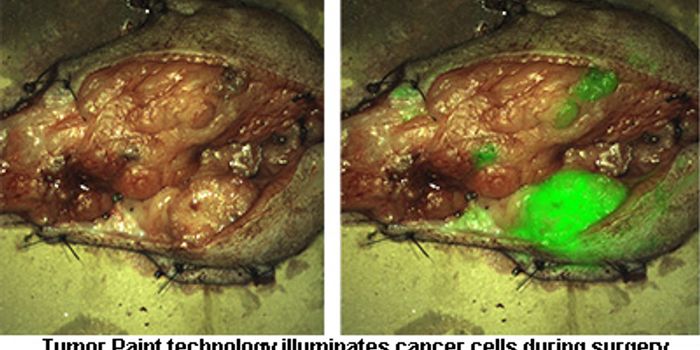

OCT 10, 2016Clinical & Molecular DXA new technique under Phase 1 clinical trial gave surgeons the ability to see a brain tumor glow like they’ve neve ...